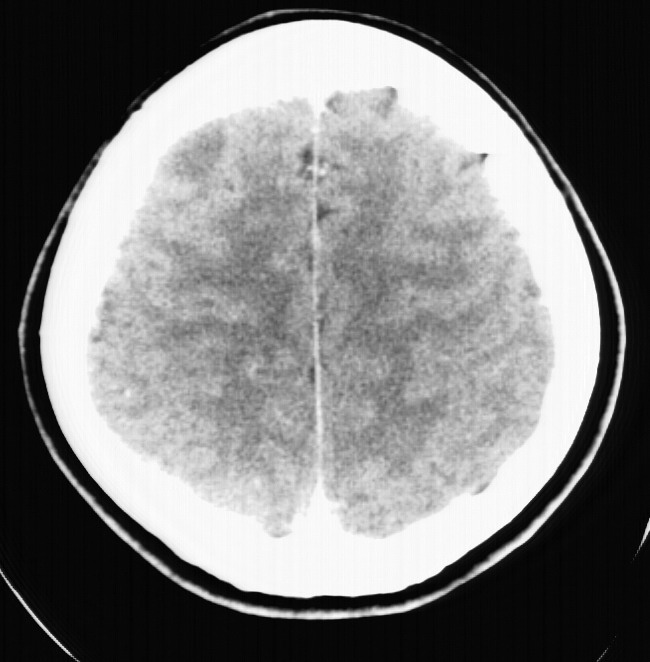

标题: CT5853:右额叶上部占位请会诊

女,34岁,自述头晕胀2年,近期感精神恍惚,无发热,实验室检查阴性。

右顶叶靠近脑表面圆形低密度灶,周围无水肿及占位效应,增强病灶无明显强化,考虑:右顶叶低分级星型细胞瘤。

右额叶上部皮质区见类圆形低密度区,边界不清,无强化,无钙化。

支持大多数战友的意见,1级星形细胞瘤。